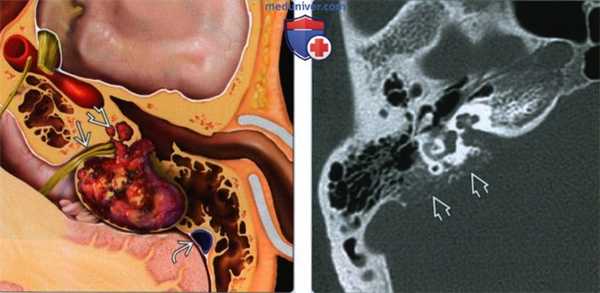

(Слева) На рисунке височной кости в аксиальной плоскости показана типичная опухоль эндолимфатического мешка (ОЭЛМ). Важные особенности: сосудистая природа, тенденция к формированию фистулы, открывающейся во внутреннее ухо, фрагменты костной ткани в матриксе опухоли. Обратите внимание на классическое ретролабиринтное расположение опухоли между ВСК и сигмовидным синусом.

(Справа) При аксиальной КТ в костном окне определяются лучевые признаки ОЭЛМ, в том числе расположение в задних отделах височной кости в области эндолимфатического мешка, Са++ в матриксе опухоли с лучистыми краями, пермеативные изменения костей.